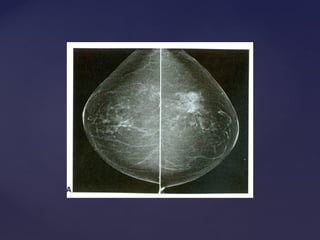

Padrão mamográficoPadrão mamográfico

Descrição Acurácia Diagnóstica

Lipossubstituídas (até 25% de tecido

glandular)

Muito alta

Parcialmente lipossubstituídas (26 a 50% de

tecido glandular)

Alta

Densas e heterogêneas

(51 a 75% de tecido glandular)

Limitada

Muito densas (>75% de tecido glandular) Limitada

Padrão mamográficoPadrão mamográfico DescriçãoAcurácia Diagnóstica Lipossubstituídas (até 25% de tecido glandular) Muito alta Parcialmente lipossubstituídas (26 a 50% de tecido glandular) Alta Densas e heterogêneas (51 a 75% de tecido glandular) Limitada Muito densas (>75% de tecido glandular) Limitada